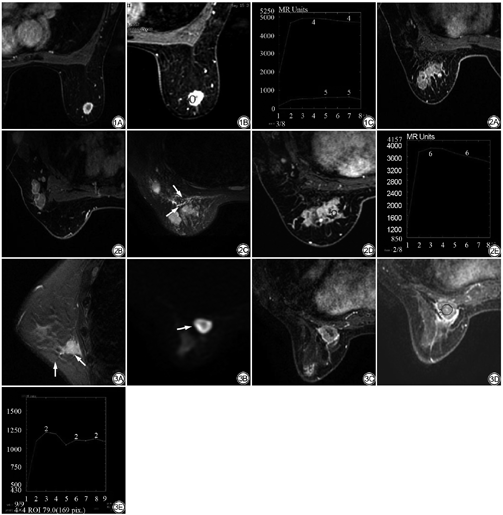

由表1可知,4种分子亚型乳腺癌病灶大小差异具有统计学意义(C=0.197,P=0.021),在≤2 cm的乳腺癌中,Luminal A型占70%(见图1),所占比例明显大于其他3组乳腺癌;而病变>2 cm乳腺癌,HER-2过表达型乳腺癌比例在4组乳腺癌中最高(62.5%)。不同分子亚型乳腺癌形态差异具有统计学意义(C=0.247,P=0.015),非肿块型病变最多见于HER-2过表达型乳腺癌(41.7%)(见图2),而三阴性乳腺癌多表现为圆形或卵圆形肿块(84%)(见图3)。不同分子亚型乳腺癌的MRI强化方式具有统计学意义(C=0.251,P=0.012),4种分子亚型乳腺癌中三阴性乳腺癌表现为环状强化的比例最高(64%)(见图3),HER-2过表达型表现为环形强化比例最低(25%)。不同分子亚型乳腺癌TIC曲线类型差异具有统计学意义(C=0.253,P=0.011)。Ⅲ型TIC曲线最多见于三阴性乳腺癌(92%),而在Luminal A型中所占比例最低(68%)(见图1);5.6%的Luminal B型乳腺癌表现为Ⅰ型TIC曲线,其他三型均未表现为Ⅰ型TIC曲线。不同分子亚型乳腺癌的部分伴随征象亦具有统计学意义:瘤周水肿(C=0.233,P=0.003),腋窝肿大淋巴结(C=0.189,P=0.029)。瘤周水肿更常见于三阴性乳腺癌(52%)(见图3),Luminal A型乳腺癌较少见到瘤周水肿(其出现率为18%)。Luminal B型及HER-2过表达型乳腺癌患者(见图2)具有腋窝肿大淋巴结的比例分别为45.8%、50%,明显高于Luminal A型(34%)及三阴性(32%)乳腺癌患者。不同分子亚型乳腺癌患者绝经状态、MRI图像边缘及乳腺背景实质强化 (background parenchymal enhancement,BPE)表现无统计学意义(P>0.05)。

Bae等[11]研究结果表明,不同分子亚型乳腺癌形态、边缘及强化方式差异具有统计学意义,并且三阴性乳腺癌更多的表现为类圆形、边界清楚等相对良性的MRI形态特征。文洁等[12]研究发现,环形强化多见于三阴性乳腺癌。本研究结果与上述报道基本一致,84%的三阴性乳腺癌表现为类圆形,64%表现为环形强化。可能与三阴性乳腺癌恶性程度高,生长速度快,从而易出现中央坏死有关。而HER-2过表达型乳腺癌多为非肿块(41.7%)、非环形强化(66.7%)。虽然本研究显示不同分子亚型乳腺癌的边缘特征差异无统计学意义(P<0.05),但是在三阴性乳腺癌中,48%表现为边缘清晰,与HER-2过表达型及Luminal B型相比,比例较高。这与王琪等[13]研究结果一致,可能与三阴性乳腺癌侵袭性高,边缘微血管密度高、纤维增生有关[14]。